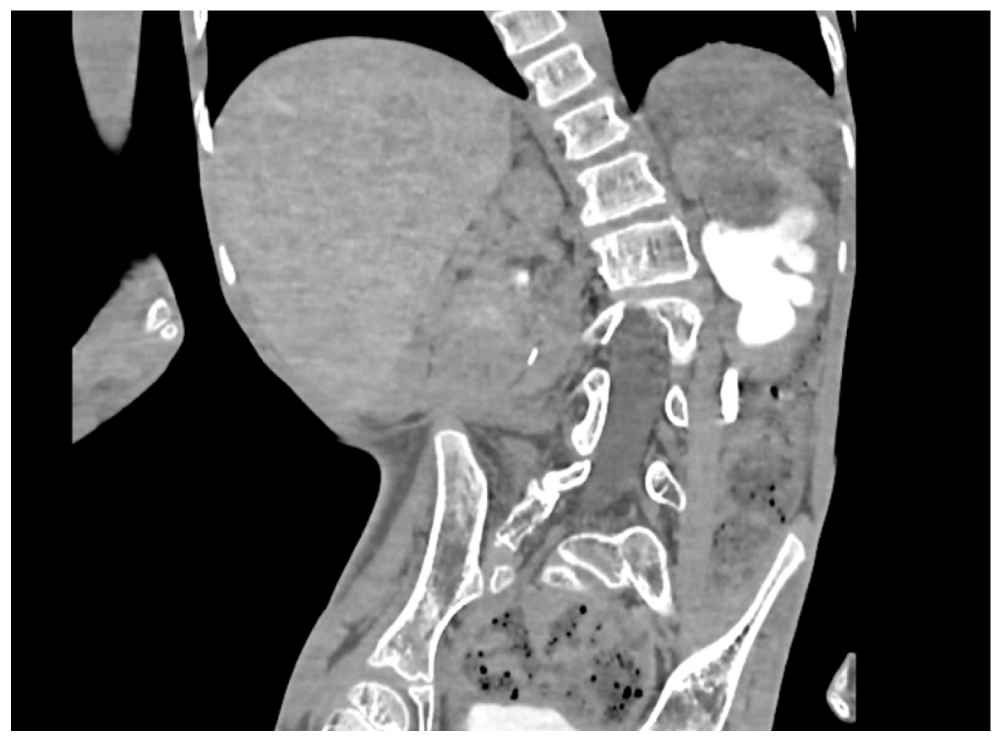

Результаты физикального, лабораторного и инструментального исследования

Ребёнок с рождения страдал неврологическими расстройствами в виде спастической квадриплегии в результате перенесённой во время родов асфиксии. Заболевание сопровождалось выраженной деформацией скелета в виде сколиоза и нейрогенными нарушениями отведения мочи. Предоперационная рентгенологическая оценка анатомии и функции почек включала ультразвуковое исследование (УЗИ) почек и мочевого пузыря, контрастную компьютерную томографию (КТ) почек и микционную цистоуретрографию (МЦУГ). С помощью УЗИ, КТ и МЦУГ оценили степень дилатации почечной лоханки и мочеточника левой почки, а также наличие камня на уровне проксимального отдела мочеточника. Лоханка левой почки была расширена до 50 мм, как и мочеточник, отходящий от неё, диаметром до 15 мм. Размеры камня составляли 18 × 10 мм. Предполагалось, что камень образовался на фоне периодических задержек мочеиспускания на фоне основного заболевания поражения центральной нервной системы. Детальное изучение КТ-сканов указало на наличие стриктуры мочеточника, расположенной сразу над камнем (рис. 1). Мочеточник ниже камня не был расширен. По данным МЦУГ везикоренальный рефлюкс не определялся. Данные радионуклидного исследования обнаружили снижение почечной функции слева до 40%.

Рис. 1. Изображения компьютерной томографии урографии, демонстрирующие наличие камня в левом мочеточнике и наличие стриктуры, расположенной выше него.

Fig. 1. Computed tomography urography images showing the stone in the left ureter and stricture located above it.